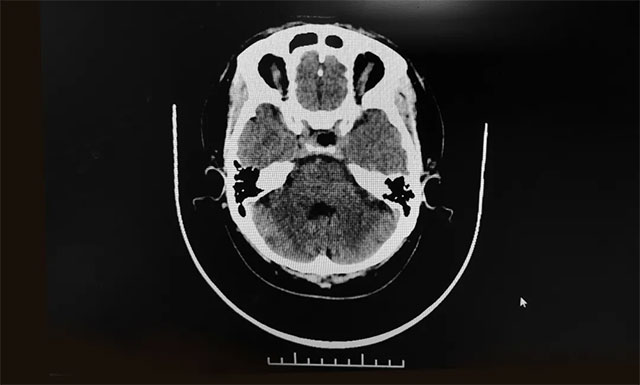

在征得患者家屬同意后,9月18日,李士其教授在吳治群博士和黃秀夫醫(yī)生協(xié)助下經(jīng)蝶竇入路成功為患者進行了手術,在蔡司顯微鏡(雙熒光)下順利將患者鞍內(nèi)腫物切除。術后患者視物異常癥狀消除,目前患者恢復良好,已康復出院。

▲ 術后影像顯示腫瘤被切除